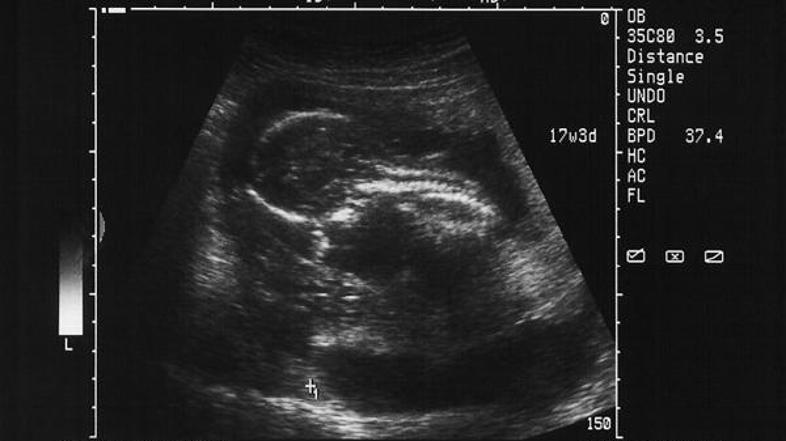

Edini učinkoviti metodi na vplivanje na spol nerojenih otrok sta PGD in Microsort, tehnika, ki loči spermo z X kromosomi od sperme z Y kromosomi pred oploditvijo. Pri metodi PGD iz vsakega z biomedicinsko pomočjo oplojenega zarodka izvlečejo celico, ki jo nato analizirajo in poiščejo kromosome, ki pomenijo spol zarodka, kar zdravnikom omogoča, da izberejo zarodek, ki ga želijo.

ZDA so ureditve o izbiranju spola uvedle leta 2001 in prav je to bil poglavitni razlog, da so ameriški zdravniški centri deležni velikega zanimanja britanskih pacientov, ki so izvedeli o njihovi pomoči pri izbiri spola otroka prek oglasov na spletu. Predimpletacijska genetska diagnoza (PGD), ki lahko razkrije spol zarodka, je v Veliki Britaniji sicer dovoljena le v primeru iskanja genetskih bolezni.